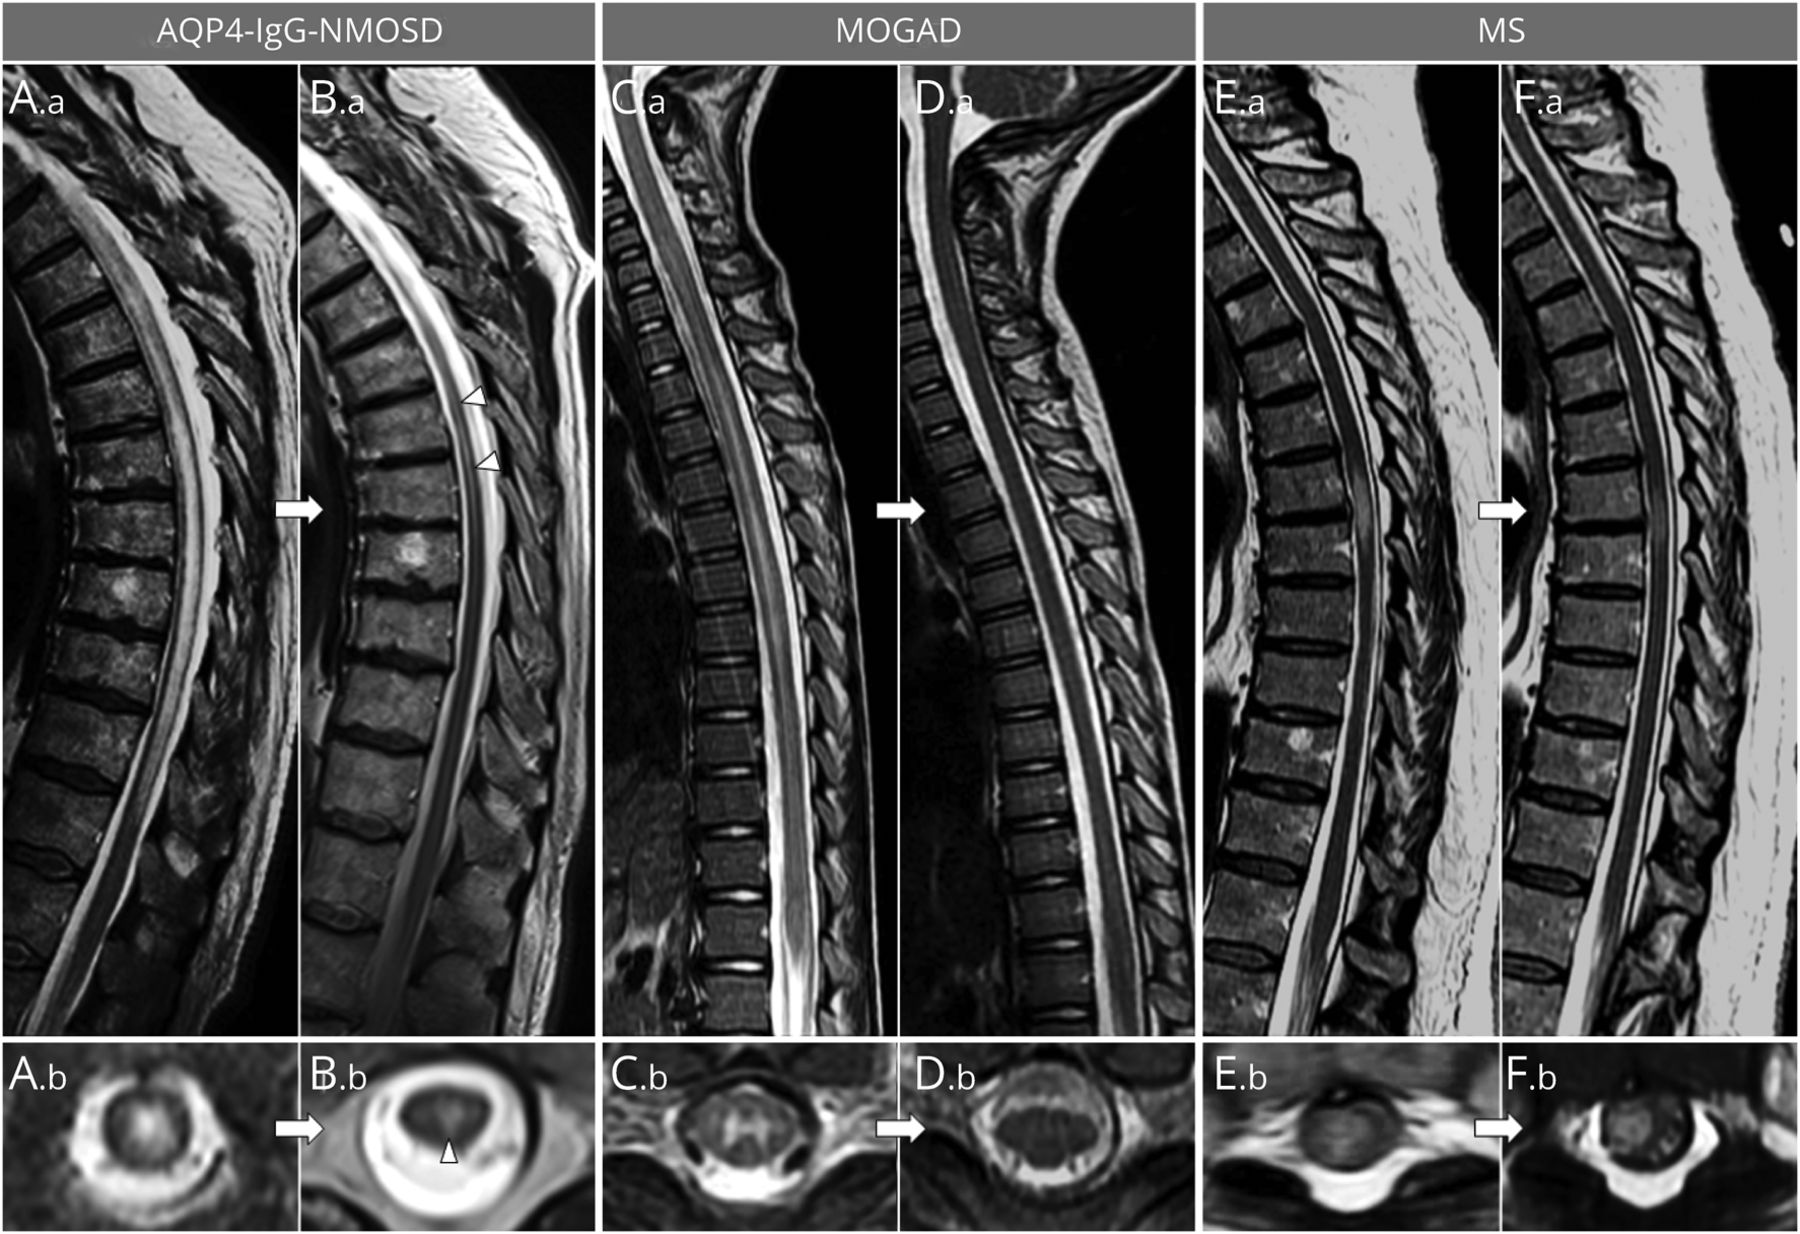

轴向fluid-attenuated反转恢复infratentorial (A, C, E)和幕上的(B, D, F)脑部MRI显示。AQP4-IgG-NMOSD患者(A、B),大急性病变。a、B。a) commonly show a prominent reduction of their initial size but rarely resolve completely, typically leaving tiny residual abnormalities (A.b, B.b; red circles). In patients with MOGAD (C, D), most large acute T2-hyperintense lesions (C.a, D.a) resolve to undetectable (C.b) at follow-up MRI, although some acute T2 lesions can leave some (often nonspecific) small foci of T2 hyperintensity (D.b; red circle). In patients with MS (E, F), acute T2-hyperintense lesions are relatively smaller (E.a, F.a) and typically show moderate reduction in size at follow-up, while remaining clearly detectable (E.b, F.b; red circles).